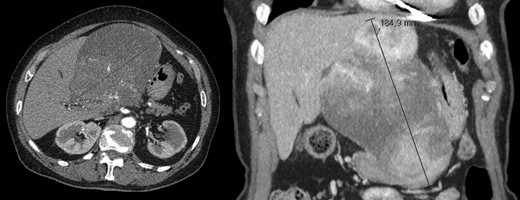

A 40-year-old woman with past medical history of c-section at the age of 26, was referred to our Hepatobiliary Unit in 2013, with diagnose of liver tumor with 16.6 cm (Fig. 2) suggestive of solitary fibrous tumor.

Abdominal Magnetic Resonance – heterogeneous liver mass in segment 4 with 16.6 cm.

No distant metastasis was identified.